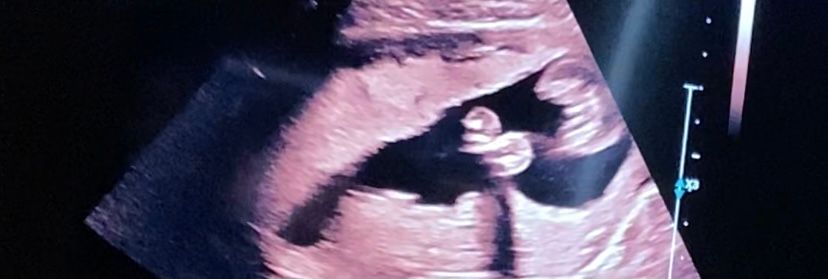

Ну это точно же девочка?

УЗИ, КТГ, доплер18 недель .

Вот на первой фотке вижу пирожок,а на второй бугорок 🤷♀️ Это обе фотки между ножек.

Вес -230 грамм,рост 18 см. Лежит поперёк,я и чувствую удары ножкой всегда слева. Вот и сама ножка ,2.30 см😂

Без сомнений девочка. У сына в 17 недель было видно все очень хорошо. Не спутать с девочкой 😂Поздравляю!!!